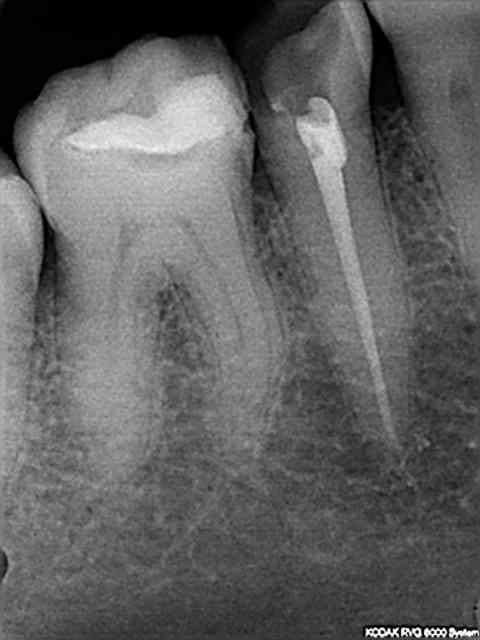

Sans problème, mais voici aussi la radio de controle du premier cas.

L'autre cas date d'hier soir une 45 non infectée mais fracturée.

Pas de canaux latéraux mais une obturation aisée avec juste un petit dépassement de ciment.